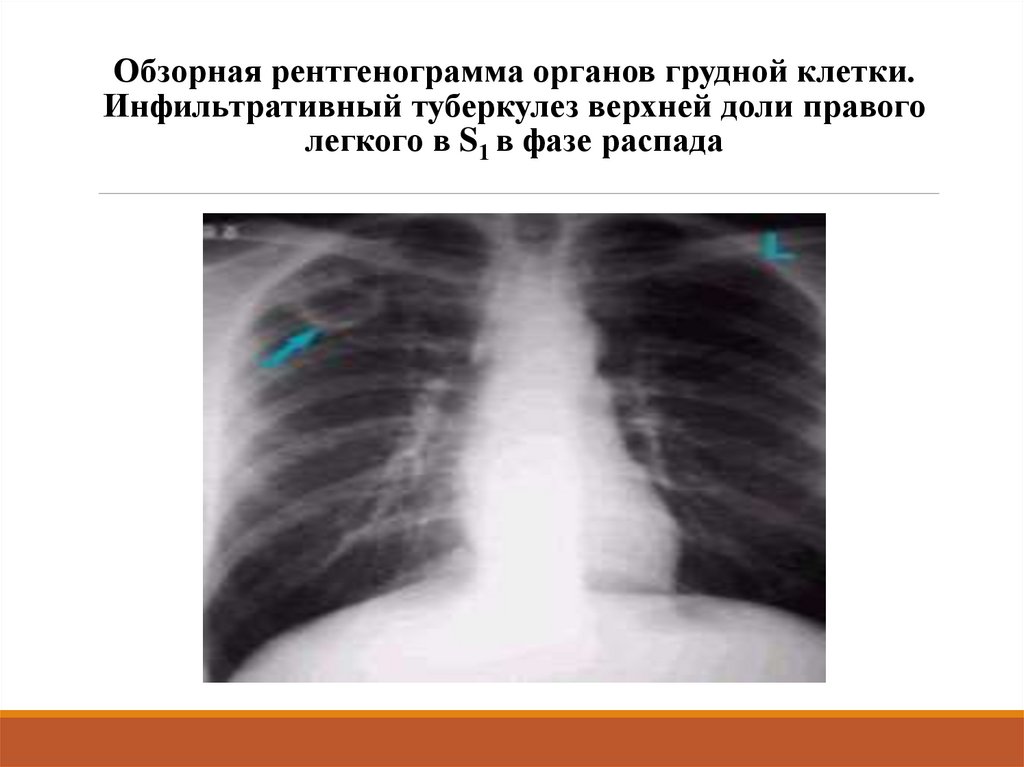

Очаговый и инфильтративный туберкулез презентация - 94 фото